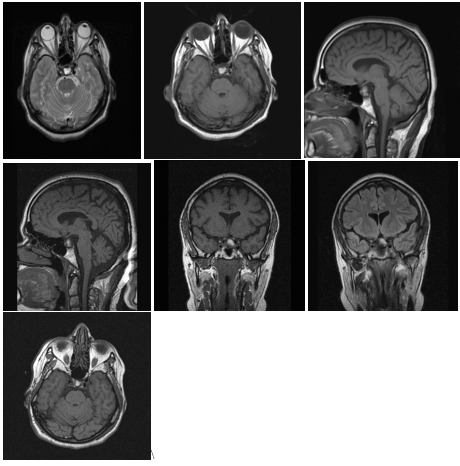

• MRI showed a homogenous mass in the sellar region with moderate suprasellar extension, the lesion was displaying high intensity signal both on T1 and T2 weighted images…which was compatible with:

MRI Diagnosis

• Cystic Craniopharyngioma

• Pituitary Apoplexy

• Or a Rathke’s Pouch Cyst

• (Figure 5)

• The study shows the region; fossa filled with soft tissue lesions with cystic components.

• The lesion is contained in the Sella turcica with the pituitary gland probably displaced, the pituitary stalk is in the midline. There are bilateral foci of hyper density signals in the white matter.

• The ventricular system and the cerebral hemispheres are normal.

Figure 5 Preoperative MRI on 01.07.08.

Conclusion: findings are consistent with post-operative changes? Ischemia of small vessel disease